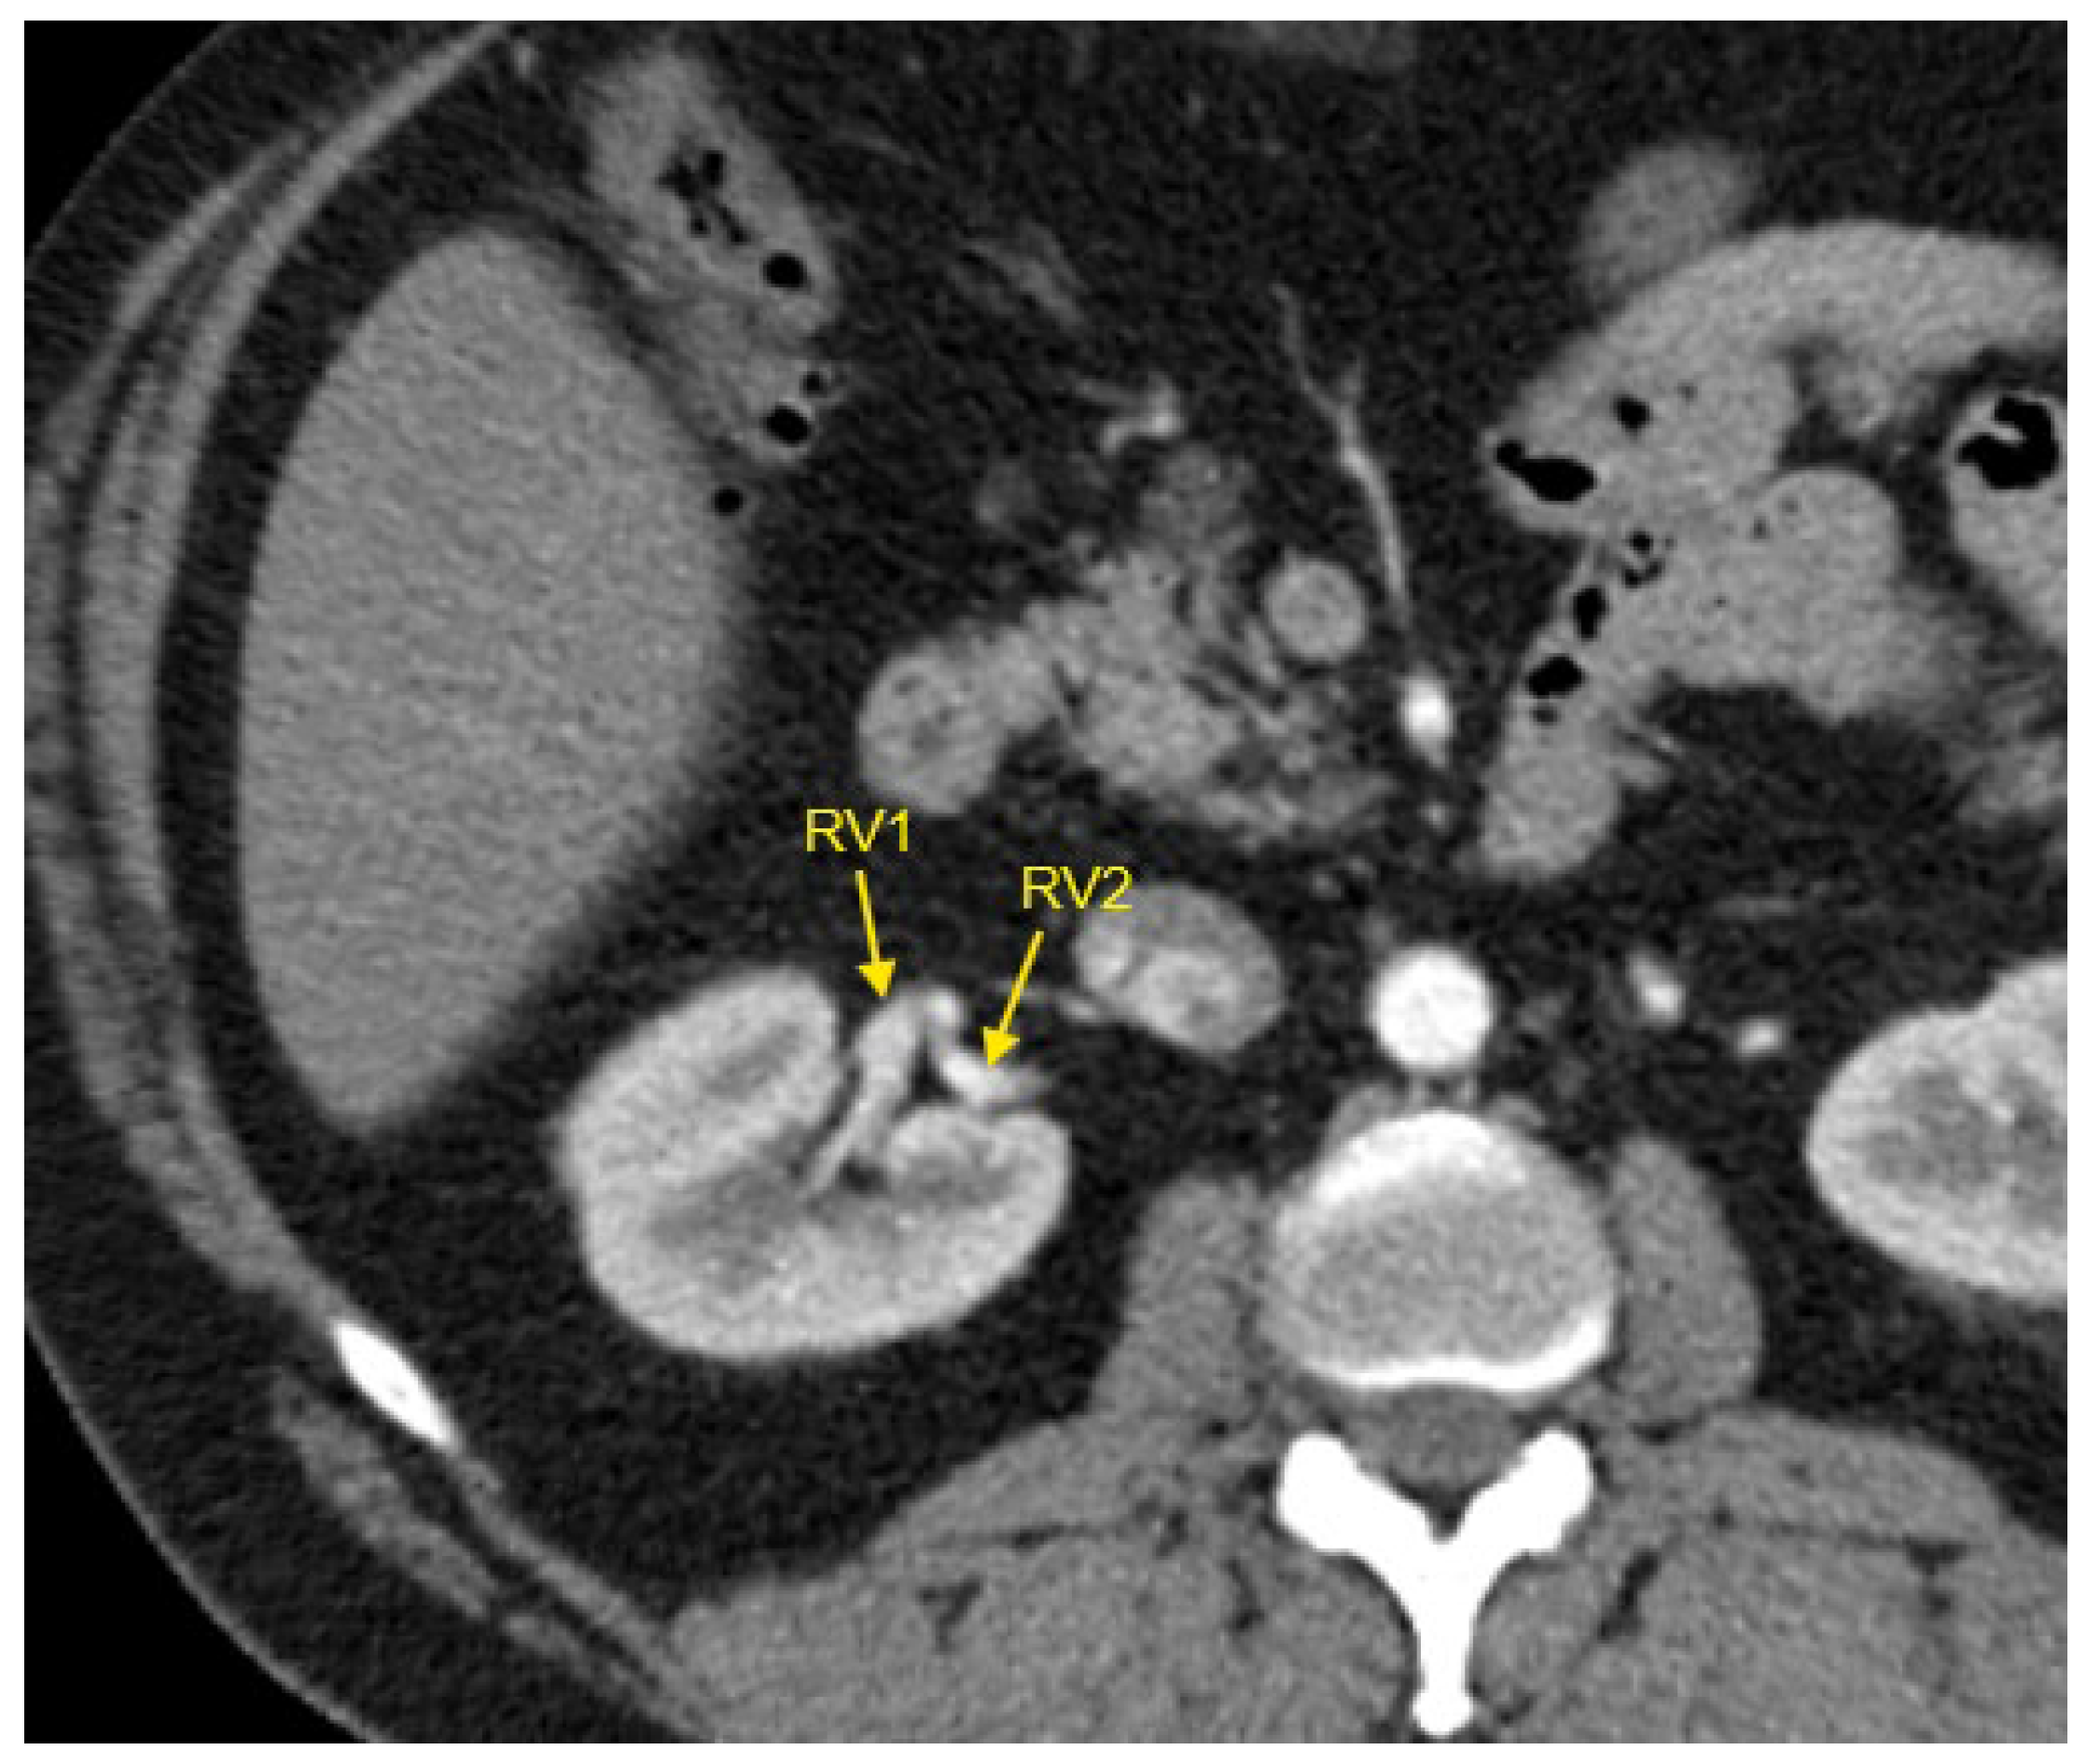

Figure 1, Figure 2, Figure 3, Figure 4 and Figure 5 show examples of some renal vascular abnormalities we identified in our study population.

Figure 5. Contrast-enhanced CT imaging of a 44-year-old male hypertensive patient with difficult-to-control HTN revealed two renal veins in the right kidney, marked by the yellow arrows. CT—computed tomography; HTN—arterial hypertension; RV1—first renal vein; RV2—second renal vein.